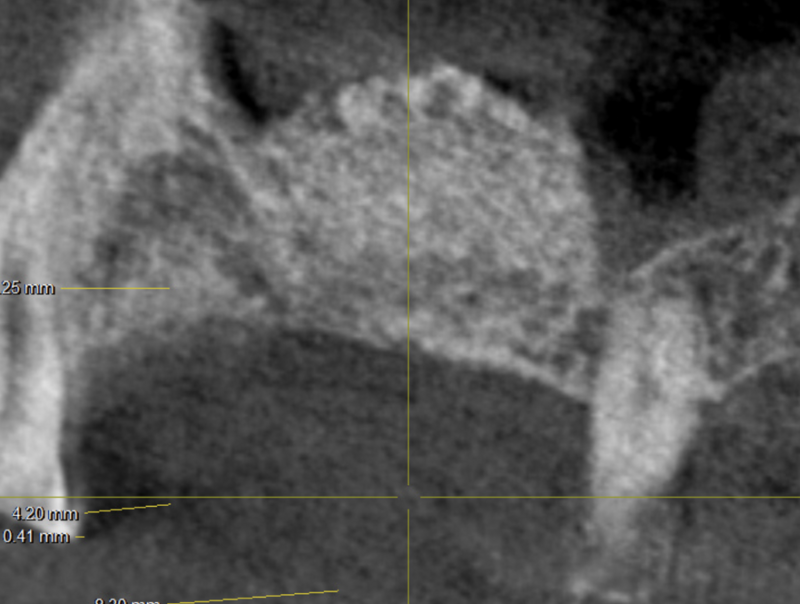

GREFFE OSSEUSE SOUS SINUSIENNE ET RECONSTRUCTION DE CRETE EN EPAISSEUR

AVANT APRES ELEVATION OSSEUSE SOUS-SINUSIENNE